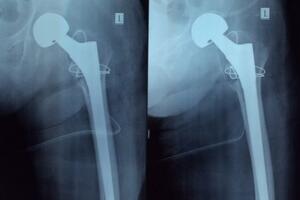

- Xương trên cánh tay và chân

Khác với ung thư vú và bệnh ung thư tuyến tiền liệt, ung thư phổi có khả năng di căn tới xương trên cánh tay và chân. Vì cánh tay và chân là hai bộ phận cử động nhiều nhất nên khi bị ung thư phổi di căn đến thì bệnh nhân sẽ phải thường xuyên chịu những cơn đau nhức xương hành hạ.